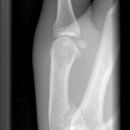

Mittelgliedbasisfraktur